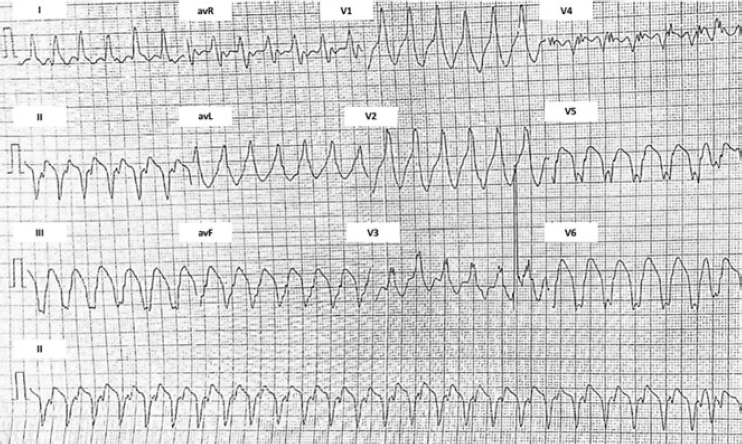

Se presenta el caso de un varón de 51 años sin antecedentes médicos. Un mes antes de su ingreso comenzó con palpitaciones rápidas asociadas a diaforesis, náuseas y vómitos. El electrocardiograma y el Holter mostraron episodios recurrentes de taquicardia ventricular monomórfica (figura 1). En la exploración física se encontró un soplo expulsivo aórtico que aumentaba con la maniobra de Valsalva. La ecocardiografía transtorácica mostró una hipertrofia septal asimétrica obstructiva, con un diámetro septal máximo de 32 mm (figura 2A), un gradiente de 65 mmHg en el tracto de salida del ventrículo izquierdo y un movimiento anterior sistólico de la válvula mitral con insuficiencia moderada. La resonancia magnética cardiaca evidenció una fibrosis miocárdica extensa como factor de riesgo de muerte súbita (figura 2B y vídeo 1 del material adicional). Se inició tratamiento con amiodarona, propranolol y, como prevención secundaria, se implantó un desfibrilador automático. El paciente reingresó a los 4 meses en tormenta eléctrica, con múltiples descargas apropiadas por el dispositivo implantado. Se administró sedación profunda, ventilación mecánica y soporte hemodinámico, y se decidió realizar un bloqueo del ganglio estrellado; sin embargo, la evolución fue desfavorable y el paciente persistió con episodios de taquicardia ventricular, lo cual motivó una cartografía electrofisiológica (sistema CARTO 3, Biosense Webster, Israel). Se intentó, sin éxito, la ablación de un circuito de macrorreentrada septal del ventrículo izquierdo relacionado con la taquicardia ventricular clínica (figura 2C).

Figura 1. Electrocardiograma inicial. Taquicardia ventricular, origen en el septo medio e inferior del ventrículo izquierdo.